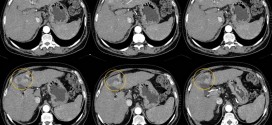

TUMOR HEPÁTICO

El tumor hepático. El hígado se encuentra en la parte superior derecha de la cavidad abdominal, debajo del diafragma y por encima del estómago, el riñón derecho y los intestinos. Este órgano con forma de cono es de color marrón rojizo y pesa aproximadamente tres libras (1,36 kg). El hígado está formado por dos lóbulos principales, ambos compuestos por miles …

TUMORES MALIGNOS HEPÁTICOS PRIMARIOS

Los tumores malignos hepáticos primarios. Durante los primeros años de vida de una persona, las células normales se dividen más rápidamente para permitir el crecimiento. El cuerpo está compuesto por billones de células vivas. Las células normales del cuerpo crecen, se dividen formando nuevas células y mueren de manera ordenada. Una vez que se llega a la edad adulta, la …

TUMORES HEPÁTICOS METASTÁSICOS

Los tumores hepáticos metastásicos. Durante los primeros años de vida de una persona, las células normales se dividen más rápidamente para permitir el crecimiento. El cuerpo está compuesto por billones de células vivas. Las células normales del cuerpo crecen, se dividen formando nuevas células y mueren de manera ordenada. Una vez que se llega a la edad adulta, la mayoría …